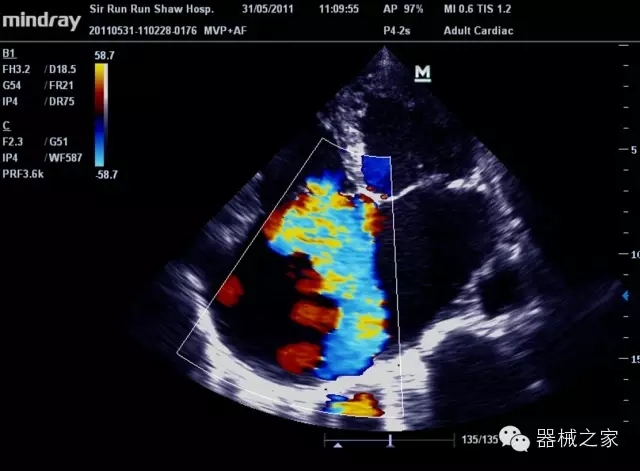

臨床圖片賞析

產(chǎn)品特點(diǎn)

·裝載有采用Multi-Core多核處理的非嵌入式平臺,成像效率大大提高,并且能夠給用戶帶來高速、多任務(wù)并行信號處理體驗(yàn);

·優(yōu)秀的圖像效果、強(qiáng)大的功能體驗(yàn)、豐富的探頭選擇、合理的便攜式設(shè)計(jì),全中文顯示及病人管理界面,使得M7在任何場合、任何時(shí)候都能快速響應(yīng)更好的心血管、腹部、婦產(chǎn)、小器官等常規(guī)超聲檢查以及肌骨、神經(jīng)、顱腦、術(shù)中等新興領(lǐng)域的使用需求;

8倍波束并行處理系統(tǒng)

·在便攜式緊湊平臺上采用更多倍波束并行接收信號處理模式,無論二維還是彩色血流圖像狀態(tài)下,擁有更靈敏的回波頻移捕獲能力,大大提高時(shí)間分辨率,尤其使得心血管表現(xiàn)更為突出;